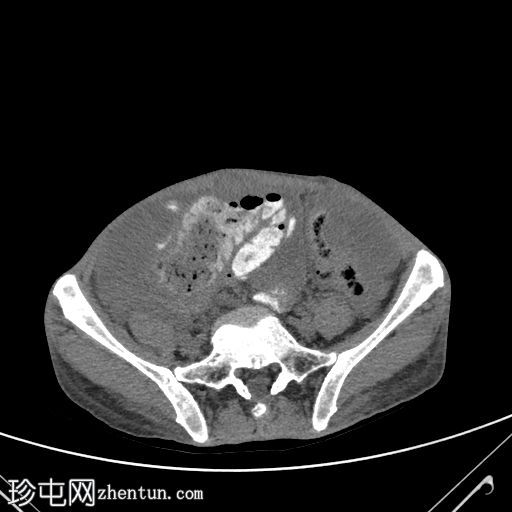

轴位口服增强扫描

大网膜和肠系膜内可见低密度、不均匀的腹膜积液,脏器表面呈扇形凹陷,尤其以肝脏和脾脏最为明显。

直肠穹窿可见一处厚度 1.2 cm、长 4.0 cm 的增强壁增厚。可见病灶周围及骶前淋巴结肿大,最大者直径 1.6 cm。

左下腹可见末端结肠造口。